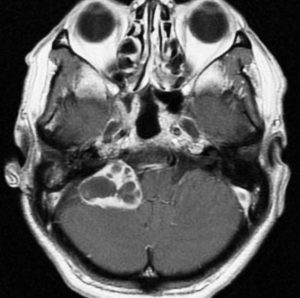

症例:頸静脈孔から頭蓋内へのもの

頸静脈孔を中心に頭蓋底骨の破壊 erosionがみられます。小脳延髄角部に進展して延髄を圧迫しています。聴神経を圧迫して聴力低下で発見された,迷走神経鞘腫です。頸静脈孔内発生のものは脳槽内の迷走神経根から腫瘍を剥離することができます。

手術直後のMRIです。頸静脈孔より深い位置にある腫瘍まで摘出しようとすると,舌咽,迷走,副神経を損傷しますから,最深部の部分だけ残して摘出しました。

手術後14年が経過しますが,無治療で残存腫瘍は縮小しました。術後神経鞘腫の自然経過ではよく観られることです。

ですから,無理して全摘出しない。